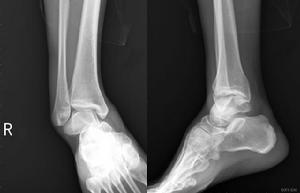

檢查

影像學檢查,踝關節脫位診斷並不困難,常規X線攝片很容易證實上述診斷;特殊檢查CT,掃描容易檢出合併存在的微小骨折。治療